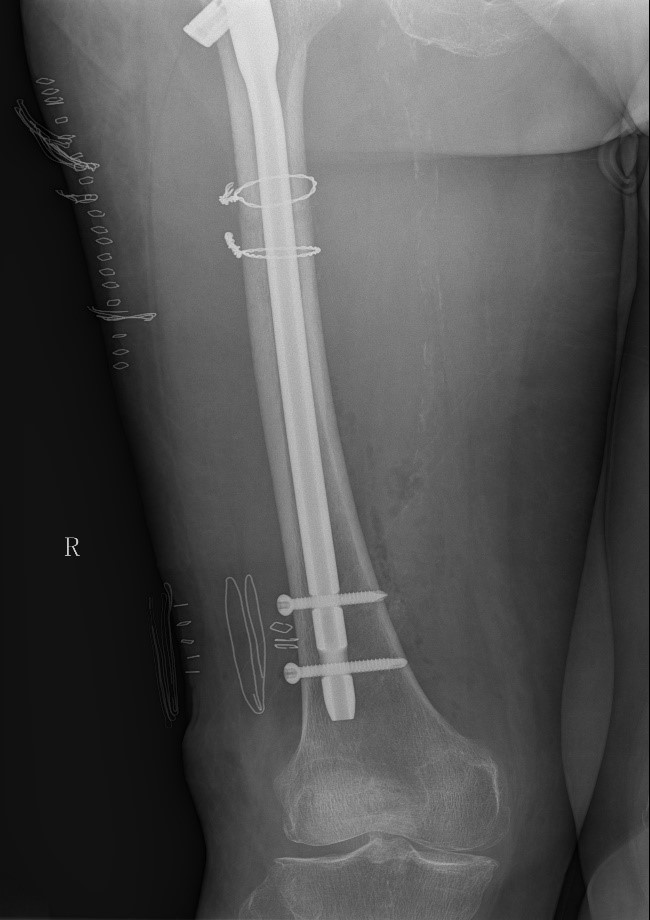

患者情况:吴先生因路面湿滑不慎摔倒,导致右髋部疼痛并活动受限,经检查确诊为股骨粗隆间骨折。

治疗难点:

1.骨折部位解剖重建的准确性;

2.内固定材料的选择及固定强度的保障。